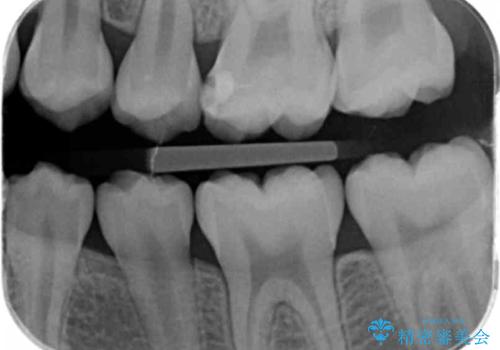

他院で治療した部分の気泡 セラミックインレーでの修復

特に症状はありませんでしたが、レントゲン上で気泡が確認されたため再治療を行っていきます。